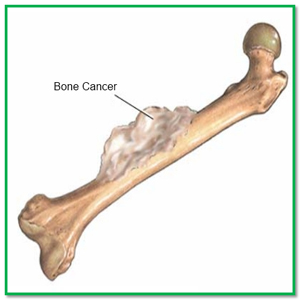

عکس سرطان استخوان. برخی از انواع اصلی سرطان استخوان عبارتند از. سرطان مغز استخوان یکی از انواع سرطان است که به دلیل اختلال در تولید گلبول ها و پلاکت های بدن به وجود می آید. رشد ناهنجار استخوان می تواند بدخیم یا خوش خیم باشد. این تصویر سرطان استخوان است که کاملا روی جمجمه قابل دیدن می باشد.

روش های عکس برداری می توانند به تعیین محل و اندازه ی تومورهای استخوان و گسترش یا عدم گسترش آن ها به سایر نقاط بدن کمک کنند. در این مقاله با علائم سرطان مغز استخوان و نیز روش های درمان آن آشنا می شوید. یک تومور رشد غیر طبیعی بافت در بدن است. سلول های توموری توانایی تنظیم کردن ندارند بنابراین سلول های بیشتری تولید می کنند و منجر به تشکیل یک توده می شوند در حالی که بسیاری از تومورها سرطانی.

تومورها و کیست های سرطان دست.